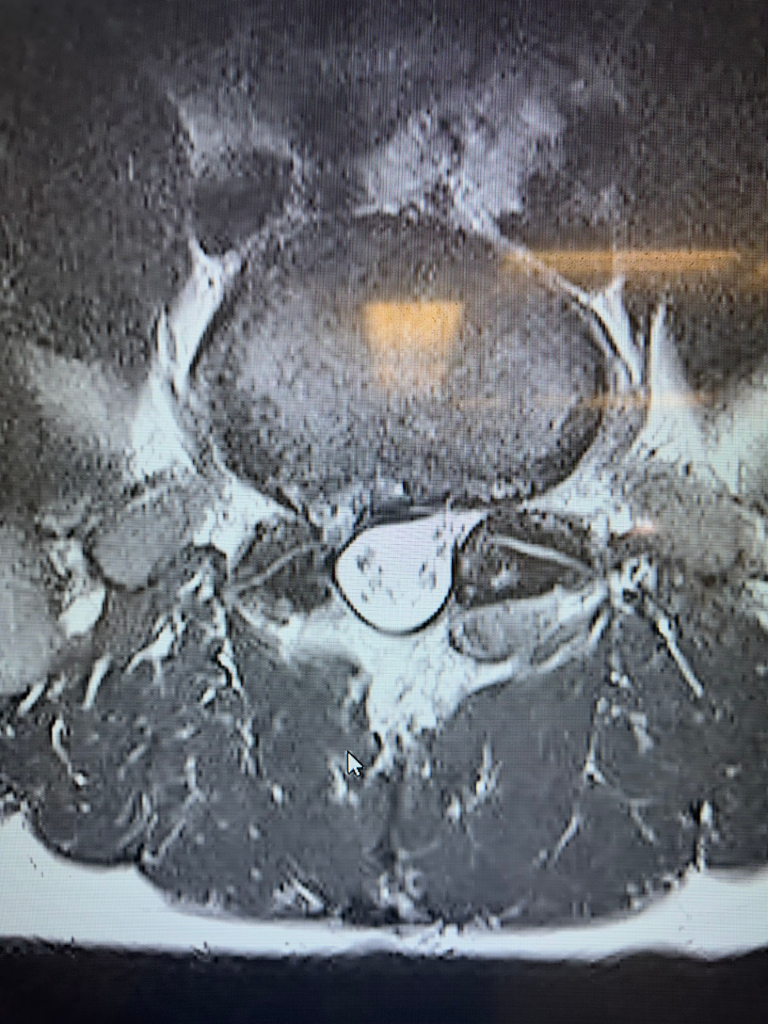

Lumbar disc replacement

Lumbar disc replacement